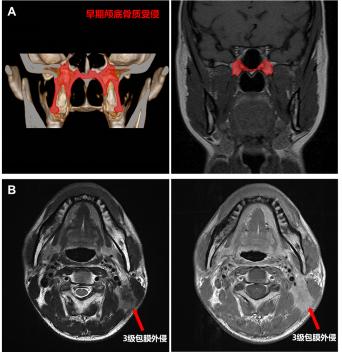

AÔçÆÚµ׹ÇÖÊÊÜÇÖ£º£º½öÓÐÒíÍ»»òµû¹Ç»ùµ×µÄµ׹ÇÖÊÊÜÇÖ

B 3¼¶ÁÜͶºÏ°üĤÍâÇÖ£º£ºÖ×ÁöÍ»ÆÆÁÜͶºÏ°üĤÇÖÕ¼ÁÜͶºÏÖÜΧÏà½ü½á¹¹